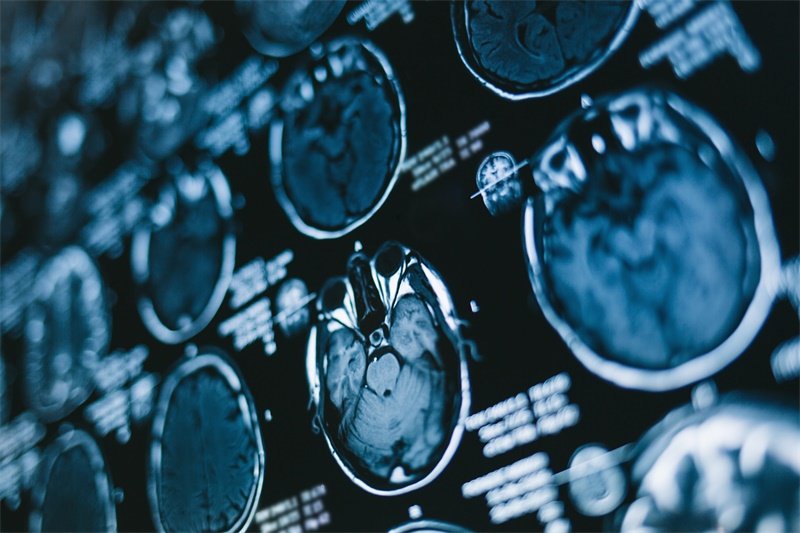

影像学检查

医学上,影像学检查是最重要的诊断工具。CT或MRI可以清晰地显示蝶鞍区的占位情况,帮助医生确定病变的性质及大小。